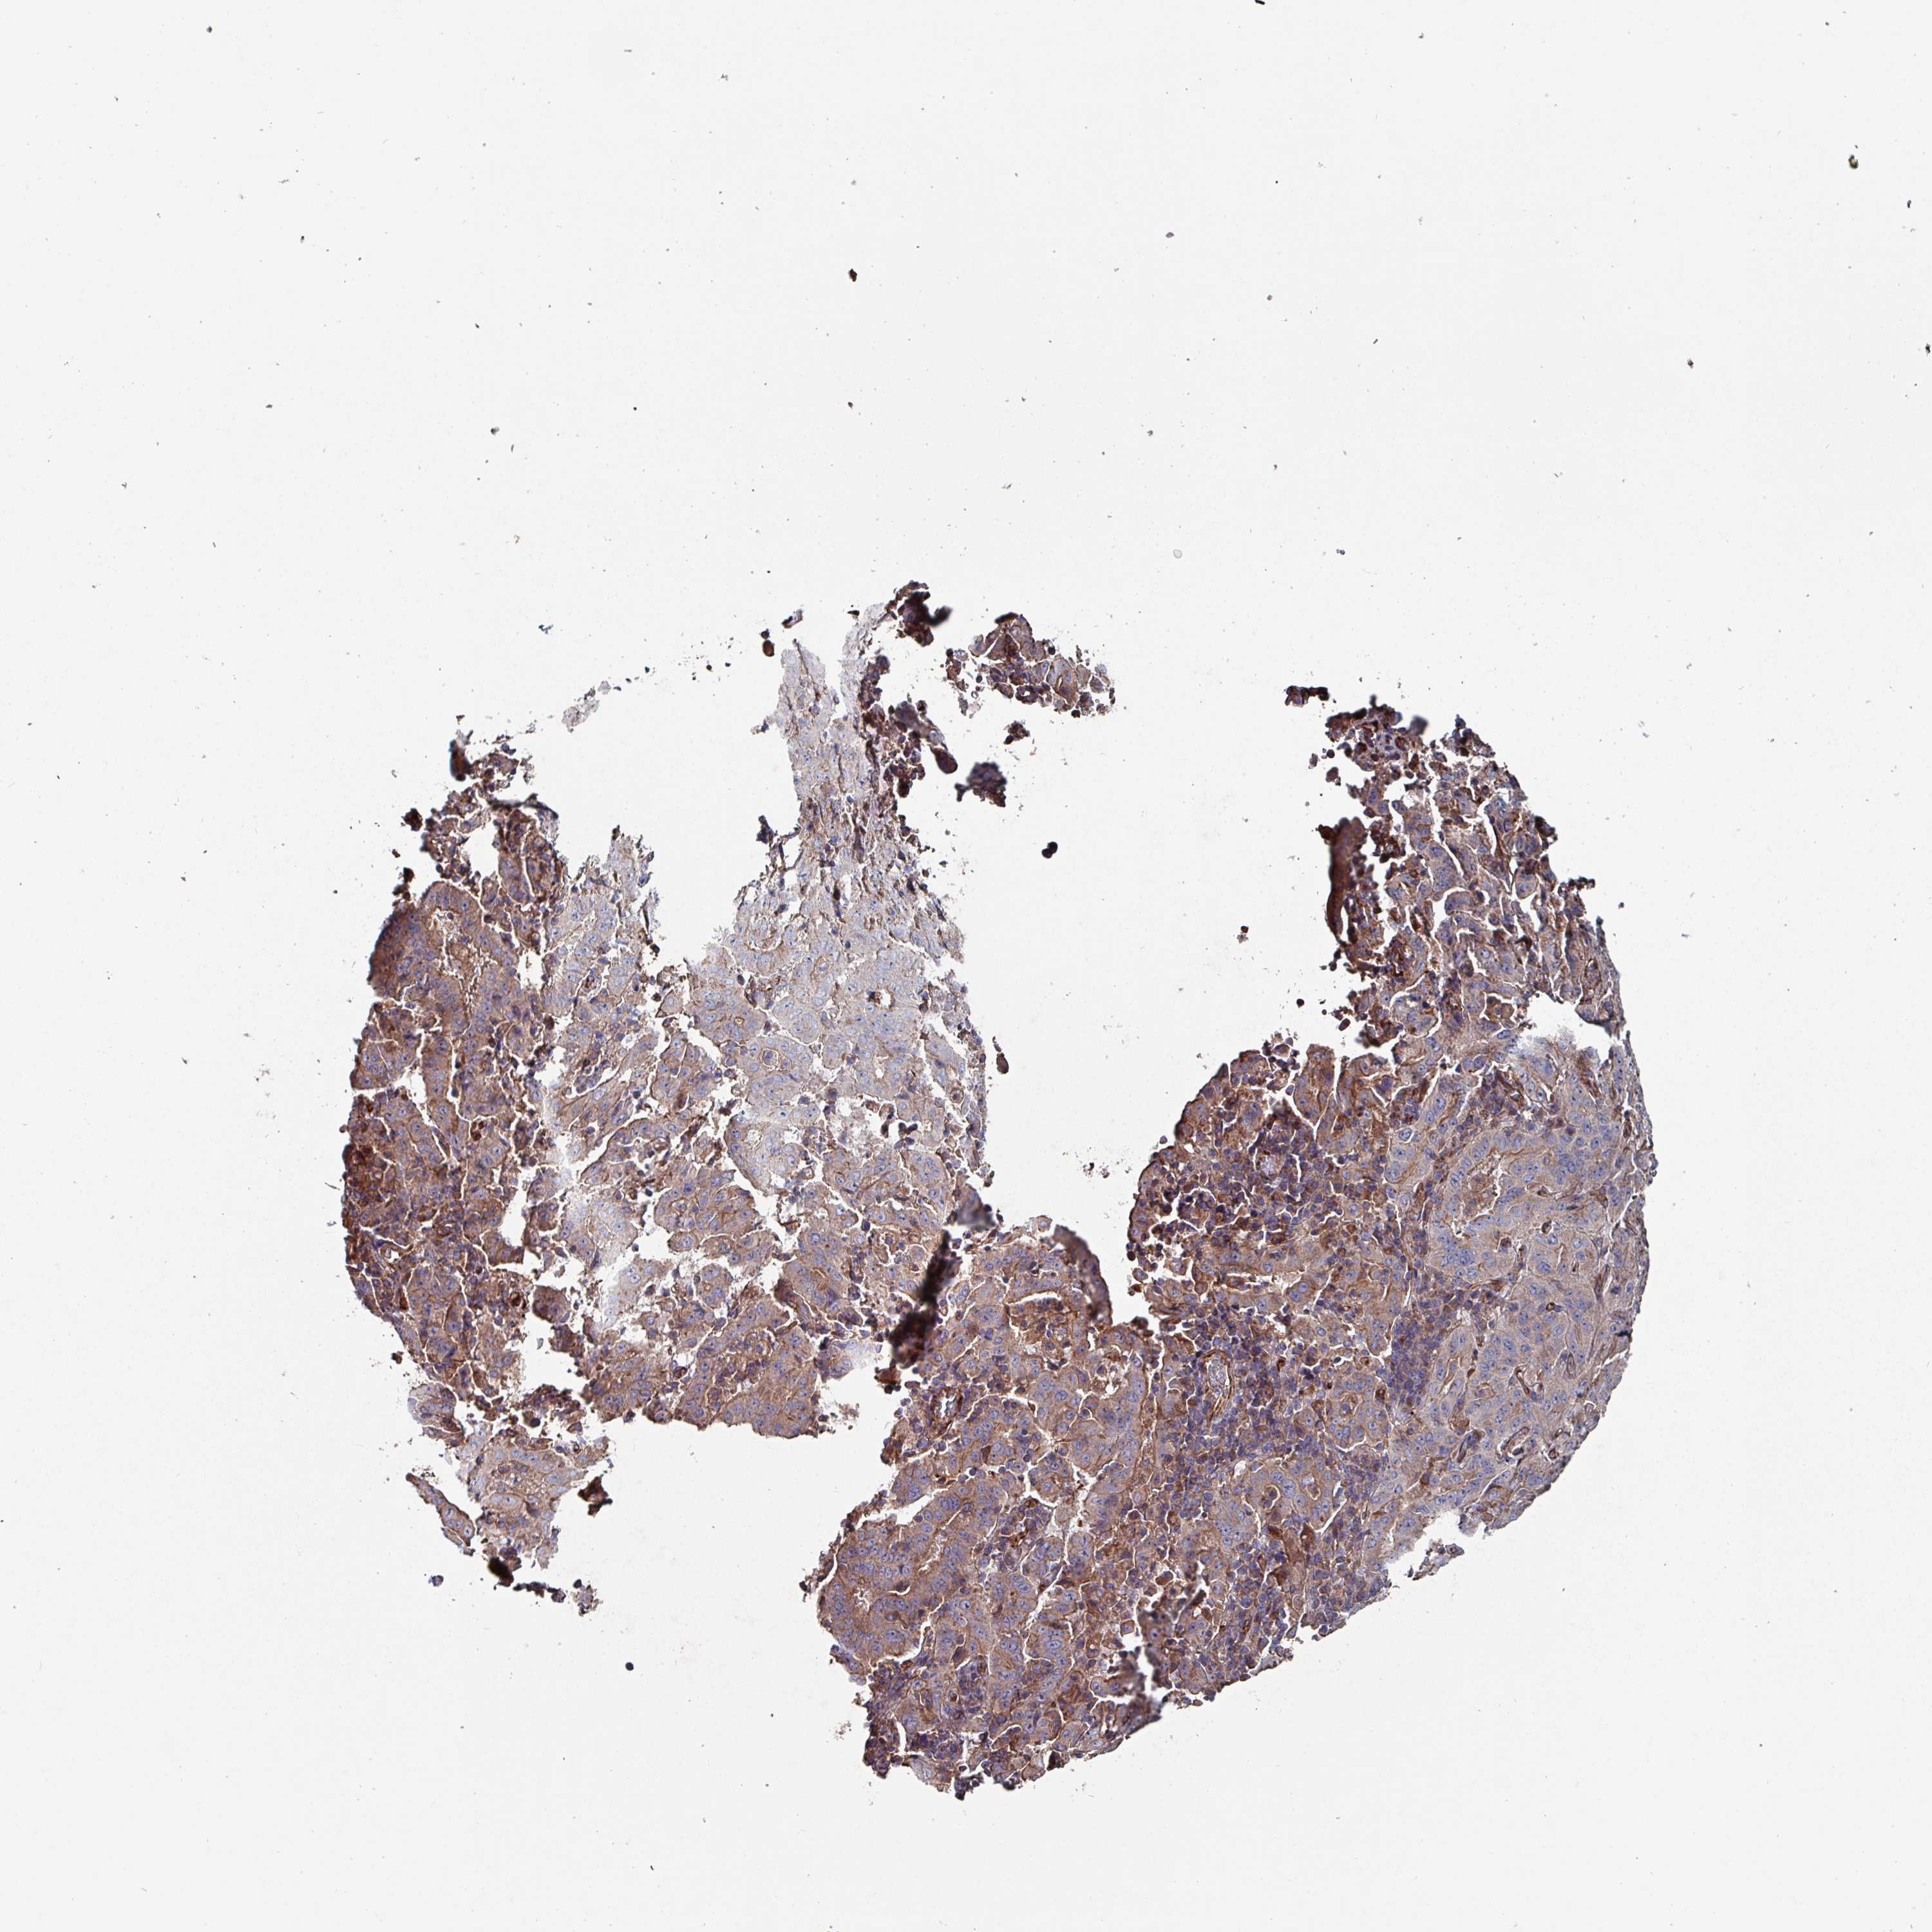

PANCREATIC CANCER - Protein expressioni

A mouse-over function shows sample information and annotation data. Click on an image to view it in a full screen mode. Samples can be filtered based on level of antibody staining by selecting one or several of the following categories: high, medium, low and not detected. The assay and annotation is described here.

Note that samples used for immunohistochemistry by the Human Protein Atlas do not correspond to samples in the TCGA dataset.

Antibody stainingi

Antibody staining in the annotated cell types in the current human tissue is reported as not detected, low, medium, or high, based on conventional immunohistochemistry profiling in selected tissues. This score is based on the combination of the staining intensity and fraction of stained cells.

Each image is clickable and will lead to virtual microscopy that enables deeper exploration of all samples and also displays staining intensity scores, fraction scores and subcellular localization as well as patient and tissue information for each sample.

Antibody HPA051569

Staining

High

Medium

Low

Not detected

Intensity

Strong

Moderate

Weak

Negative

Quantity

>75%

75%-25%

<25%

None

Location

Nuclear

Cytoplasmic/membranous

Cytoplasmic/membranous,nuclear

Adenocarcinoma, NOS